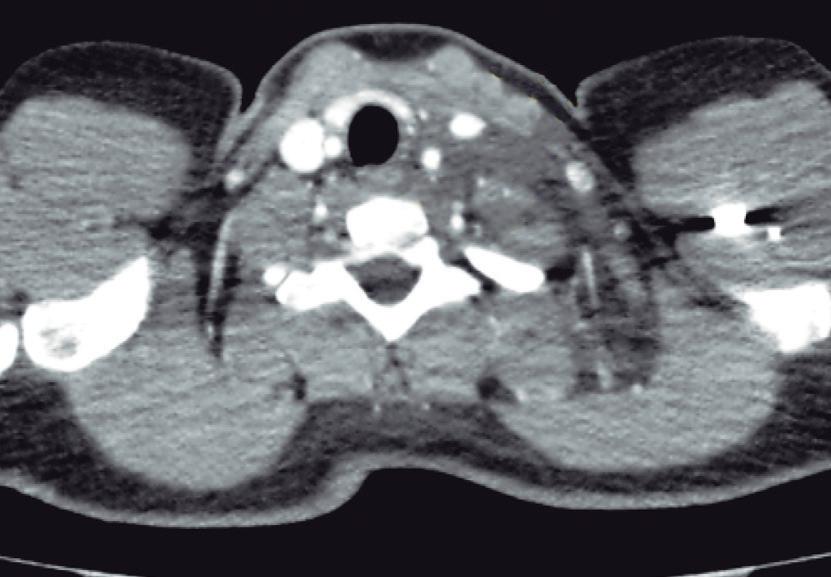

La endoscopía superior es un procedimiento fundamental para el diagnóstico, la evaluación de la respuesta al tratamiento y el monitoreo a largo plazo de la actividad de la EEo. Los hallazgos endoscópicos típicos incluyen edema (reducción de vascularidad), anillos esofágicos fijos, exudados blancos, surcos longitudinales, estenosis, estrechamiento de la luz esofágica, friabilidad de la mucosa (mucosa en papel crepé) y una consistencia firme de la mucosa al realizar biopsias (signo de “tracción" o "resistencia”) en pacientes con fibrosis (Figura 1). Estos hallazgos no son patognomónicos y no constituyen un criterio diagnóstico; sin embargo, cuando se evalúa de forma cuidadosa, en la gran mayoría de los casos se pueden observar.19-21

En el panel A se observa un esófago con edema difuso y pliegues longitudinales; en el panel B se aprecia edema con pliegues y exudados blanquecinos; en el panel C se evidencia un estrechamiento luminal acompañado de anillos esofágicos y exudados; y en el panel D se muestra un desgarro mucoso posterior a la dilatación con bujía de Savary, hallazgo esperado tras este procedimiento terapéutico.

Figura 1. Características endoscópicas de la esofagitis eosinofílica